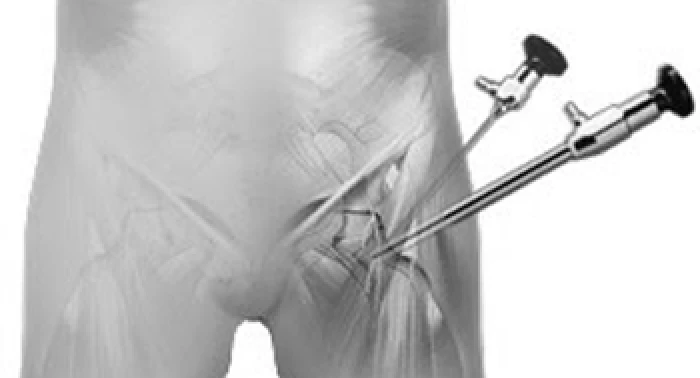

Artroscopia do Quadril

Cirurgia minimamente invasiva para tratar impacto femoroacetabular, lesões do lábrum e outras condições. Recuperação mais rápida, menos dor pós-operatória.